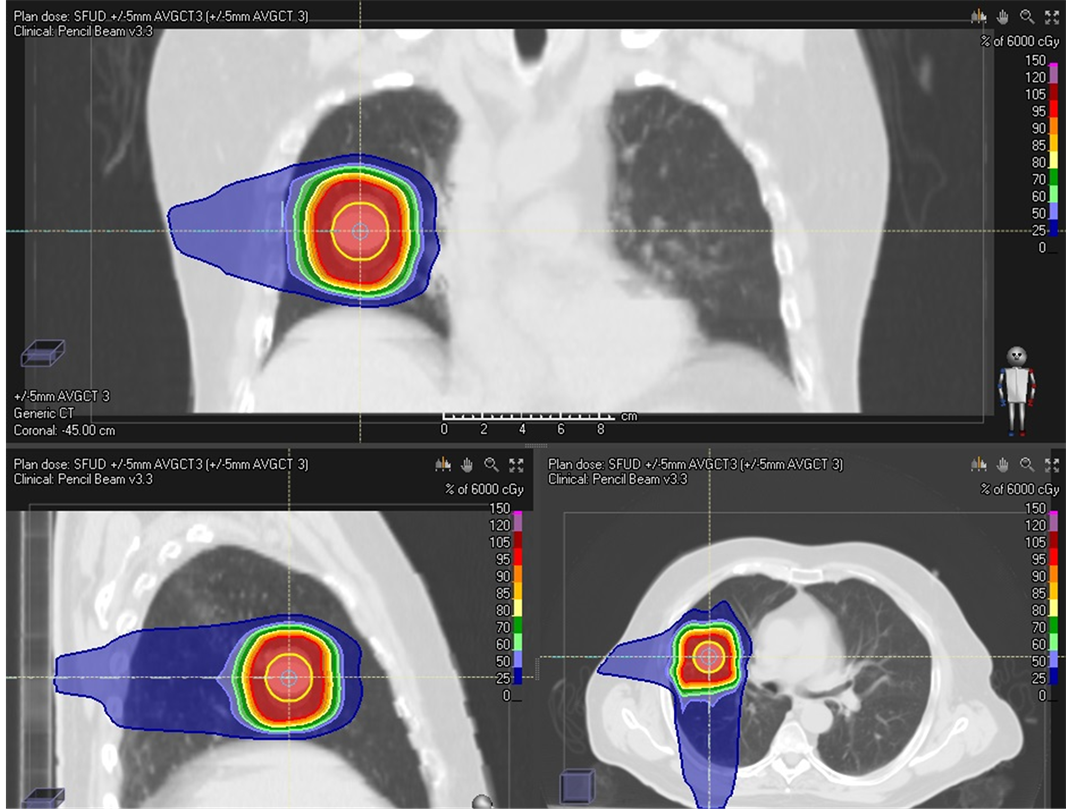

Single field uniform Dose (SFUD) proton plans were generated using posterior and right lateral beams. Plan was optimized based four initial CTs (MIP CT, CTavg_muscle, CTavg_tumor and CTavg_only) respectively. Posterior and Right lateral beams were chosen. Beam-specific PTVs (BSPTVs) were created to take into account of 3.5% +1 mm proton range and energy selection uncertainty for each beam direction which is about 6 mm anterior/posterior for PA beam and 5 mm Left/Right for RT LAT beam direction. 5 mm margin was used for all around other direction from the ITV to BSPTV except distal end. Each field covers 95% BSPTV with 60Gy and combines both field deliver 100% of the prescription dose to at least 95% PTV_eval. However, in the current clinical practice, this BSPTV expansion methodology does not take into ac- count for the WET changes between muscle and lung tissue. PTV_eval iscreated with 5 mm margin all around the ITV. The dose distribution of treatment plan based CTavg_ only was displayed on Figure 2 as an example.

Figure 2. Dose distribution for initial plan based CTavg_only.